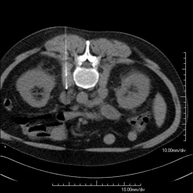

- TC Abdominopélvico

Prueba diagnóstica que consiste en obtener imágenes bi y tridimensionales del abdomen y de la pelvis de alta definición anatómica (estructuras óseas, estructuras vasculares, hígado, páncreas, vesícula biliar, riñones, glándulas suprarrenales, bazo, intestino delgado y grueso, vejiga, útero y ovarios, próstata y vesículas seminales, uréteres, etc.) mediante el empleo de un equipo de TC (Tomografía Computarizada). La mayoría de estudios requieren el empleo de contraste yodado.

- Angio-TC aorta abdominal

Prueba diagnóstica no invasiva que consiste en el estudio de la arteria aorta abdominal obteniendo imágenes de alta definición anatómica mediante el empleo de un equipo de TC (Tomografía Computarizada) y de contraste yodado. La calidad de las imágenes permite realizar reconstrucciones en 2D y 3D gracias a estaciones de trabajo especializadas en el estudio arterial. Está indicado en aquellos pacientes con enfermedad vascular (aterosclerosis), en aneurismas de aorta, en pacientes con dolor abdominal de posible origen vascular, en estudios pre-quirúrgicos de lesiones adyacentes a la aorta abdominal como "mapa" vascular, etc. La información obtenida de forma no invasiva es indispensable para los pacientes que requieren tratamiento percutáneo o quirúrgico. En aquellos pacientes que solo requieren un seguimiento de las lesiones vasculares, esta técnica es la técnica no invasiva de elección junto con la angio-RM.